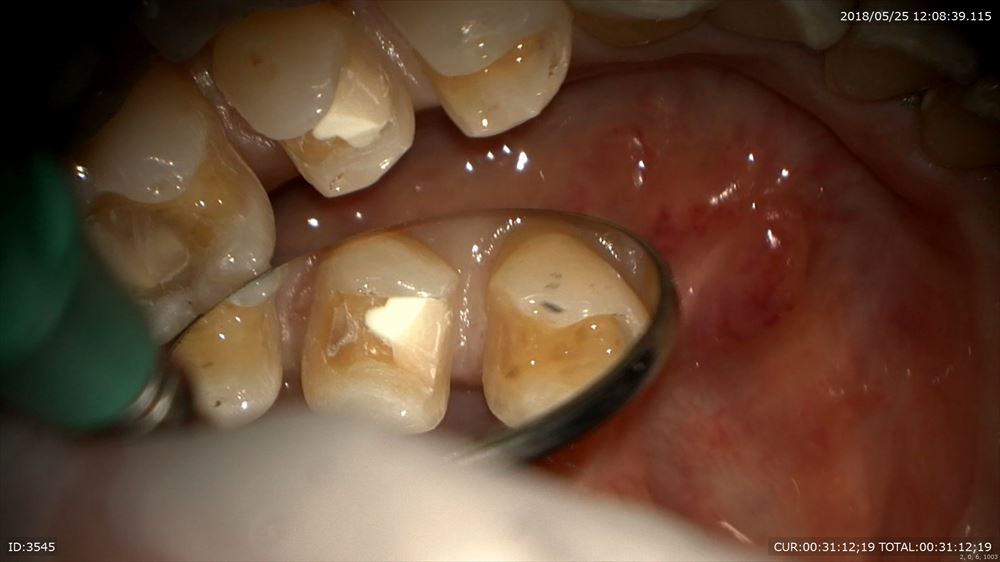

今日の修復。左下5番の修復。前回神経を保護したケース。

調整

セット

違和感も消えました。

歯茎の下までの虫歯も精密治療でこの様に2回で治ります。